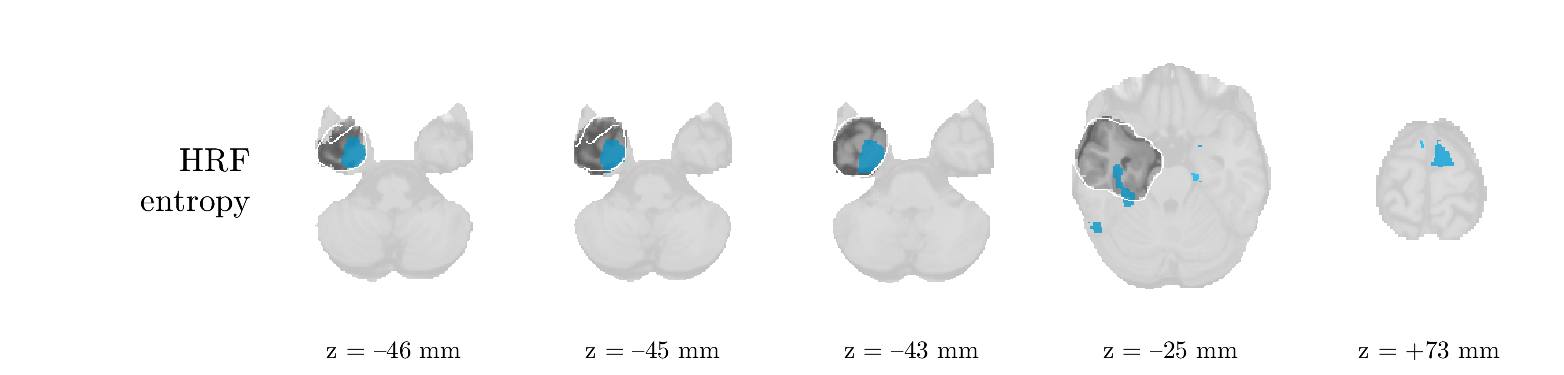

We analyze the solution with sources. Figure 1 shows the EEG signatures and HRF waveforms. One of the sources is highly correlated to the MWF reference (in grey), which was already known from Table B.3. This IED-related source had a typical low-frequency spectrum, which is expected for the typical spike-and-wave interictal discharges. The topography is relatively diffuse, although the highest amplitudes are mostly in the left hemisphere. This is in accordance with the lateralization of ictal onset zone (left temporal lobe, cfr. Table 1). There are some noteworthy observations to be made about some of the other components. The fourth has an unusually sharp spectrum, is mainly localized on two nonadjacent center electrodes, and is sustained for a single period of many seconds Hence, this component likely captured an artifact (of yet unknown origin), although we spotted no large-amplitude changes in the EEG itself. Similarly, the third source is only present at one frontal electrode, and exists in a frequency range above 20 Hz. It might represent a muscle artifact, e.g., due to frowning or twitching of some muscles in the forehead. The HRFs of all ROIs are shown in Figure 1(b). Two of the basis functions seem to have converged to a very similar waveform, which is an unfortunate possibility if two initial HRFs are too close to the same local optimum in their respective parameters. This reduces the expressive power of the basis set, which is clearly visible, since many ROIs have a nearly identical HRF. One of the twenty ROIs with the highest-entropy HRF overlapped the IOZ, although clearly this HRF (bold line) is not among the most dissimilar waveforms for this patient. This is also visible in Figure 2: both the HRF entropy and extremity maps show a small overlap with the delineated IOZ. Despite the good correspondence in the EEG domain, no significant (de)activation of the IED-component is found inside the IOZ.